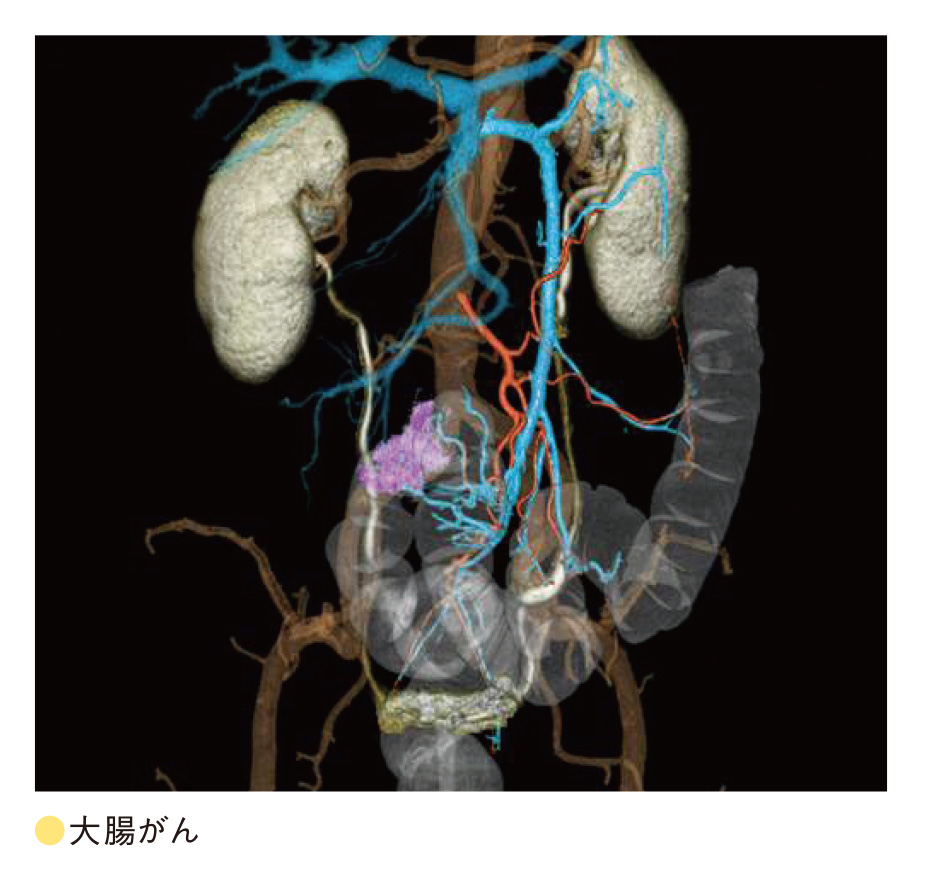

皆さん、CT検査の画像を見たことはありますか?CT画像はよく「体の輪切り画像」と表現されます。近年のCT装置の進歩は著しく、専門的な画像処理を施すことで「輪切り画像」だけでなく、様々な画像表示を行うことができるようになりました。上に示すのはほんの一例ですが、「3D画像」といって患者さまに疾患を説明する際や手術の前に綿密なシミュレーションを行う際に役立つものです。白黒のCT画像を用いて作成するのですが、色付けをすることで誰にでも疾患を理解しやすい画像となっていますこのように、現代の医療において患者様の病気を早期発見し、安心して安全に治療を受けていただく上でCT検査は必要不可欠となっています。

皆さん、CT検査の画像を見たことはありますか?CT画像はよく「体の輪切り画像」と表現されます。近年のCT装置の進歩は著しく、専門的な画像処理を施すことで「輪切り画像」だけでなく、様々な画像表示を行うことができるようになりました。上に示すのはほんの一例ですが、「3D画像」といって患者さまに疾患を説明する際や手術の前に綿密なシミュレーションを行う際に役立つものです。白黒のCT画像を用いて作成するのですが、色付けをすることで誰にでも疾患を理解しやすい画像となっていますこのように、現代の医療において患者様の病気を早期発見し、安心して安全に治療を受けていただく上でCT検査は必要不可欠となっています。

一方で、CT検査というと被ばく線量に関して不安を抱く方もいるかと思います。CT検査で受ける被ばく線量は微量であり、過度に心配する必要はありませんが、少しでも少ない被ばく線量で検査を受けたいと思うのが患者様の心理だと思います。そこで、私たちX線CT認定技師は、日額の線量を管理しつつ、患者様の疾患や治療法などに合わせて最適な検査を提供できるように、日々更新される最新技術の獲得やその有用性などを専門的に評価しています。私たちは複雑化した技術への対応を図りながらCT検査を実施し、様々な形でCT画像を提供することにより、患者様に寄り添うCT検査を目指しています。